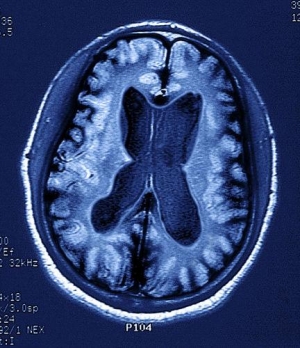

수면 부족시 알츠하이머 유발 단백질 축적

의학저널 JAMA신경학(JAMA Neurology)에 게재된 논문에 따르면 평균 연령 76세인 노인들이 충분한 수면을 취하지 못하면 알츠하이머를 유발하는 베타아밀로이드 단백질이 축적되는 것으로 나타났다.